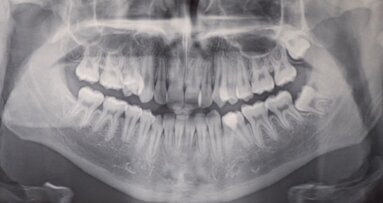

Case report Un paziente di anni 29 di sesso maschile si presenta per un controllo. In apparente salute sistemica, riferisce di avere bisogno di mostrare un sorriso luminoso e bianco poiché, essendo un odontoiatra, ha deciso di dedicarsi alla pratica clinica quasi esclusivamente estetica e cosmestica, comprese le tecniche di antiagening periorali (fotoringiovanimento e filler), e vuole valorizzare nei confronti dei suoi pazienti il suo aspetto curato e il sorriso smagliante, a mo’ di modello per corretti stili di salute orale; essere quindi testimonial esso stesso dell’efficacia delle terapie proposte.